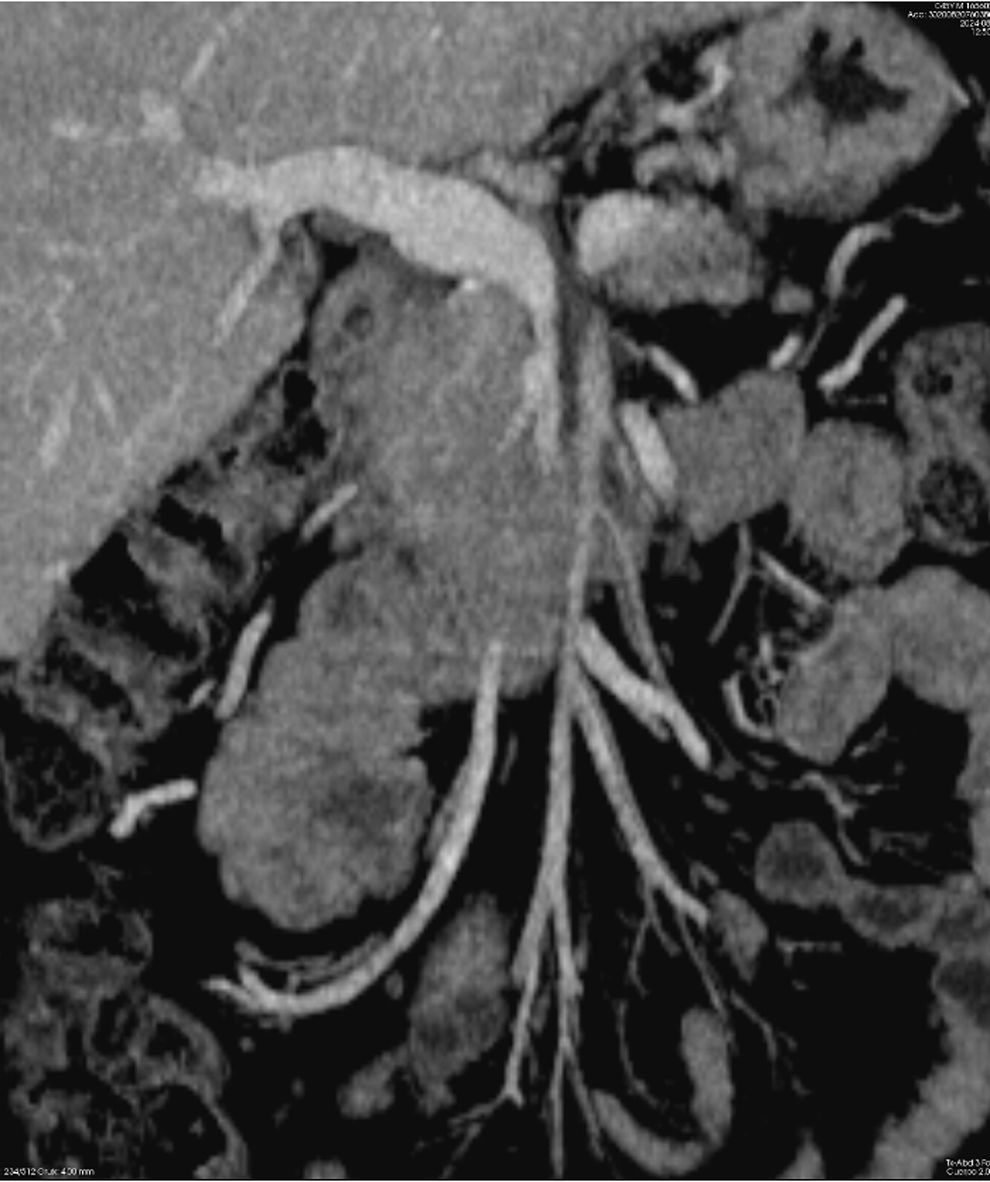

The resection of locally advanced adenocarcinoma of the pancreatic head with occlusion of the superior mesenteric vein and involvement of the splenomesenteric portal confluence (EMP) sometimes requires prolonged venous clamping with risk of intestinal ischemia. The use of intraoperative venous shunts has been published by reference groups to allow successful resection. In our centre we performed a total pancreatoduodenectomy for locally advanced pancreatic head adenocarcinoma with superior mesenteric vein occlusion (SMV) and splenomesenteric portal confluence. The use of a temporary ileo-caval shunt via a venous graft allowed resection of the tumour without repercussion on the bowel. The surgery ended with closure of the shunt, anastomosis of the graft to the portal vein and digestive reconstruction. The patient presented good tolerance to surgery and was discharged on the 7th postoperative day. The pathology report described pancreatic adenocarcinoma ypT1N0(R0) regression grade GRT2/IIa, with 0/30 affected adenopathies.

La resección de adenocarcinoma de cabeza de páncreas localmente avanzado con oclusión de la vena mesentérica superior y afectación del confluente esplenomesentéricoportal (EMP) obliga en ocasiones a un clampaje venoso prolongado con riesgo de isquemia intestinal. La utilización de shunts venosos intraoperatorios ha sido publicado por grupos de referencia para permitir la resección con éxito. En nuestro centro realizamos una duodenopancreatectomía total por adenocarcinoma de cabeza de páncreas localmente avanzado con oclusión de vena mesentérica superior (VMS) y confluente esplenomesentéricoportal. El uso de un shunt ileo-caval transitorio mediante un injerto venoso permitió la resección del tumor sin repercusión en el intestino. La cirugía finalizó con el cierre del shunt, anastomosis del injerto a la vena porta y reconstrucción digestiva. El paciente presentó buena tolerancia a la cirugía, siendo dado de alta el 7 ° día postoperatorio. El estudio anatomopatológico describió adenocarcinoma pancreático ypT1N0(R0) grado regresión GRT2/IIa, con 0/30 adenopatías afectas.